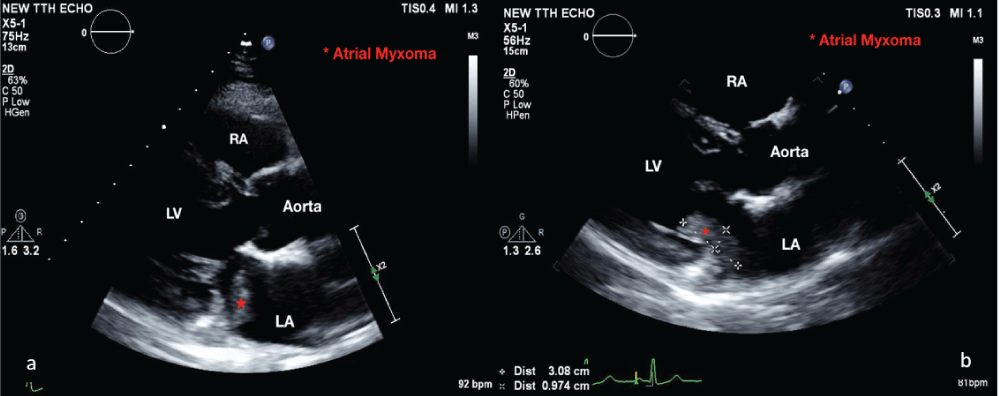

On admission, the patient was asymptomatic and vital signs revealed blood pressure of 135/80 mmHg, heart rate of 87 bpm, and oxygen saturation of 98% on room air. Laboratory analysis was unremarkable, except for hemoglobin level of 98 g/L. Electrocardiogram showed normal sinus rhythm. TTE confirmed a 4 × 1 cm mobile echo-dense mass arising from interatrial septum (LA side), and prolapsing through the mitral valve during diastole (Figure 1a and Figure 1b). The left ventricular ejection fraction (67%) and valvular function were normal. Non-stress test confirmed a reassuring fetal status in a cephalic presentation. Following discussion between cardiologists, cardiothoracic surgeons, obstetricians and anaesthetist, consensus decision was made to perform caesarean section first, with a view to proceed with cardiac surgery the following day after stabilizing the patient. She underwent an uncomplicated caesarean section with tubal ligation under general anesthesia, combined with Transesophageal Echocardiography (TEE) (Figure 2), and gave birth to a male infant, weighing 3.670 g with Apgar scores of 8 and 9 at 1 and 5 minutes, respectively. Hemi-sternotomy was employed and 30,000 Units of IV heparin was administered prior to her heart put on Cardiopulmonary Bypass (CPB) machine. A left atrial mass was resected from the interatrial septum and the defect in the septum was approximated with a patch. The CPB time was 59 minutes. The histology was consistent with a benign cardiac myxoma (Figure 3). She had an unremarkable recovery, and was discharged on day five post cardiac surgery. Short and long-term follow-ups are expected, as per cardiology clinic protocol.

Figure 1: (a) Transthoracic echocardiography demonstrating an atrial myxoma in the left atrium during systole; (b) and protruding into the left ventricle during diastole (the red asterisk indicates atrial myxoma). View Figure 1